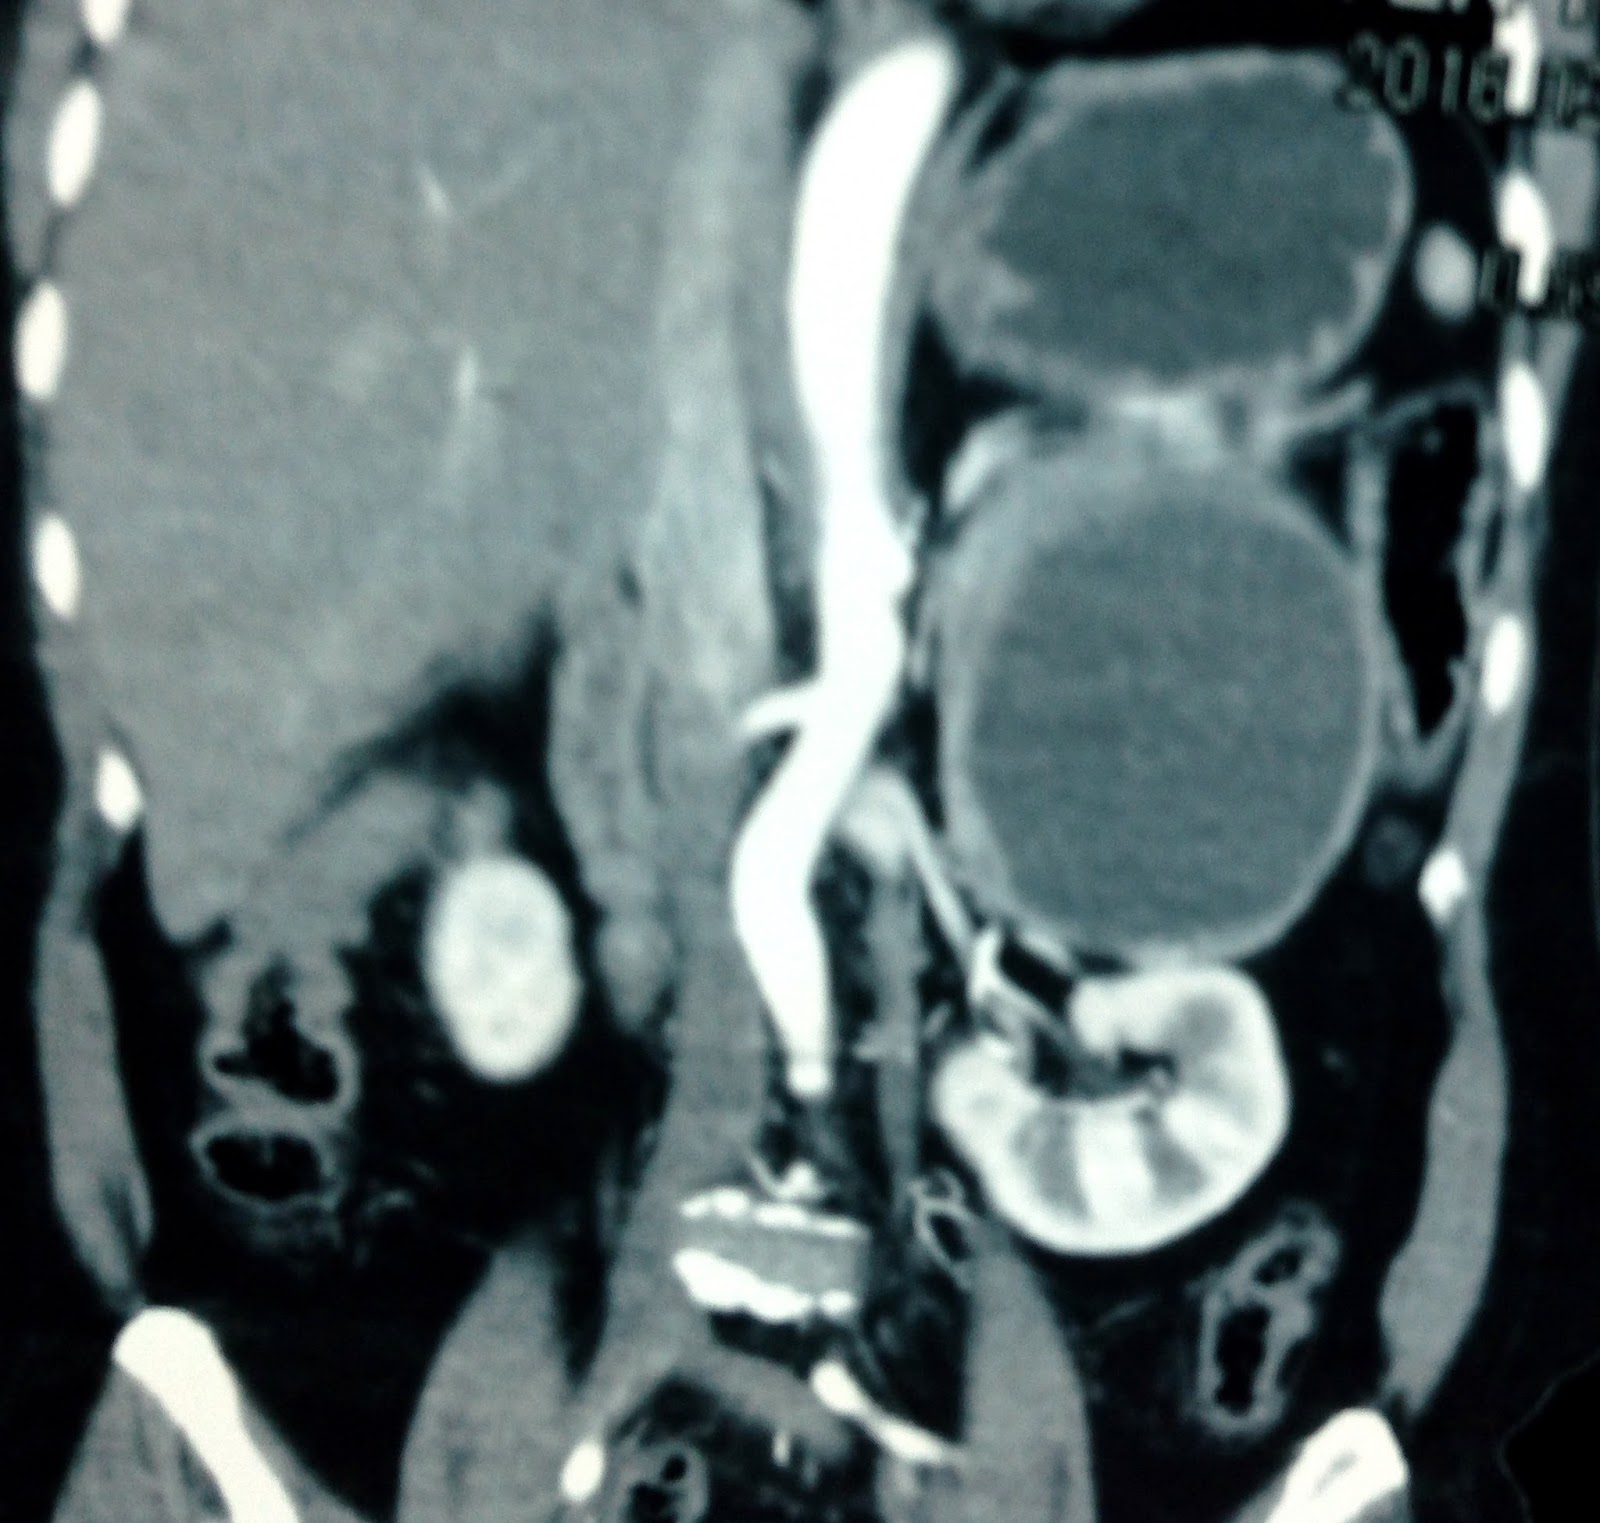

MSCT with CE= CT1: sagittal plan this mass at adrenal fossa deplaced left kidney. CT2: normal vascular supply to kidney . CT3: crossed section of.this mass inhomogeneous in contrast enhancement.